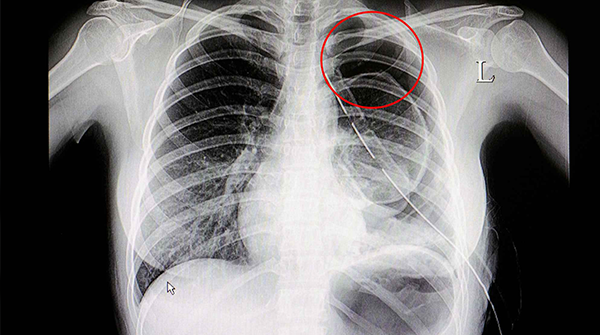

男女生做胸透检查方式都一样,按照检查步骤来准没错

胸透,即X射线。在很多情况下都是可以用到的。很多人一听到胸透,摇头就是拒绝,但其实也根本没有了解到胸透检查是干嘛的,怎么检查。或者有的人到了胸透检查前一秒也不确..